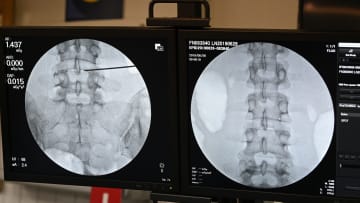

يعاني ما لا يقل عن 619 مليون شخص في جميع أنحاء العالم من آلام أسفل الظهر، ويُتوقّع أن يرتفع هذا العدد إلى 843 مليون شخص بحلول عام 2050، وفق تقديرات بحث جديد.